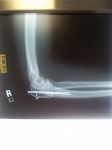

Few people know that I fell in 2013 at the beginning of the season after 36 years of successfully climbing ladders. It was a precarious situation, one that I should have walked away from but we "have" to always help our customer. A single repair on the starter course, in the back, on a hill, too many trees and no gutter. Since there was no way to stand up the 36' ladder I opted to use the stand off and approach from under the soffit with the 22' fully extended. With nothing to hold on to I found myself past the point of no return and could not fly! We guesstimated my landing spot to be about 32' (we were on a hill). I got the breath knocked out like never before, sat up and told Gabriel (no long works here) to give me a minute and I will be back to work. He let me know my elbow was a mess though there was no pain. I did have quite a bit of pain somewhere within my rib cage so off to the emergency room we go.

Two broken ribs, busted the tip off my elbow that needed surgery. I sat in the corner on a futon for two months. Sleeping in a bed with broken ribs is not an option. I tell this story to remind all of you that what we do is dangerous. Safety, safety and a little more safety! I could be on a mantle or eating out of a straw!